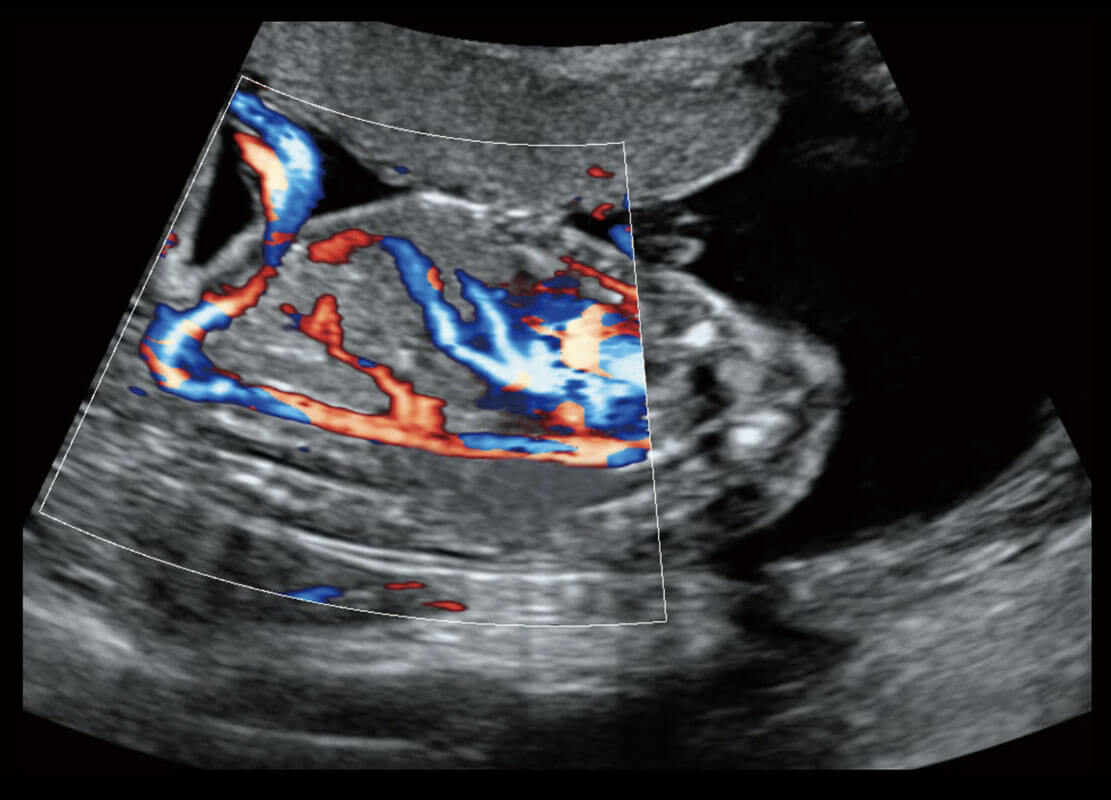

P60搭载宽频带线阵探头、宽景成像、弹性成像技术,为您提供乳腺应用方案。P60支持高频相控阵探头、线阵探头、腹部高频探头、腹部微凸探头等,丰富的探头群搭载敏感的彩色血流成像,适用于新生儿多种脏器检测要求,满足新生儿筛查需求。

新生儿肝血管癌

新生儿脊髓圆锥

新生儿心脏